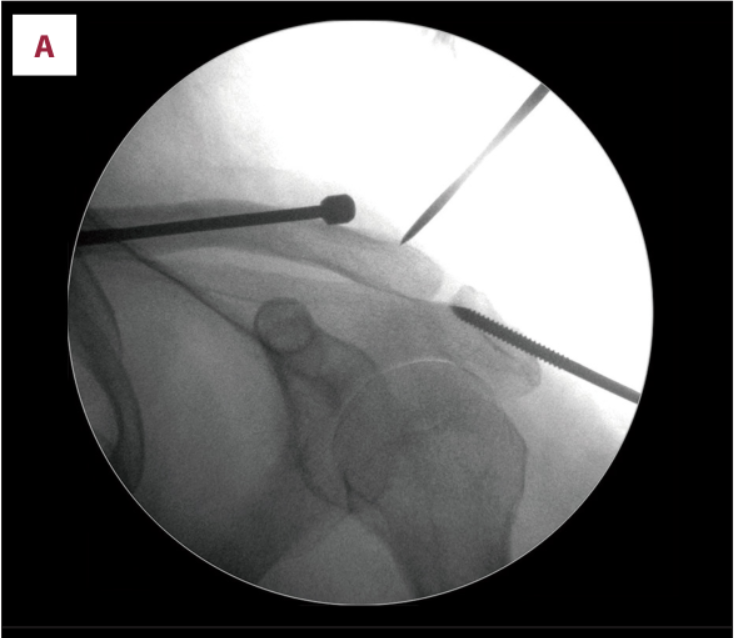

(A)在c臂图像增强器的帮助下,用克氏针将锁骨推入解剖位置进行闭合复位。(B)从肩峰尖端穿过肩锁关节(ACJ)至锁骨远端,用Knowles钉在锁骨远端后侧实现皮质锚定。采用Knowles销固定时,采用拉力螺钉技术保持ACJ空间。(C)术后x线片显示经皮Knowles针闭合复位治疗ACJ脱位复位良好。